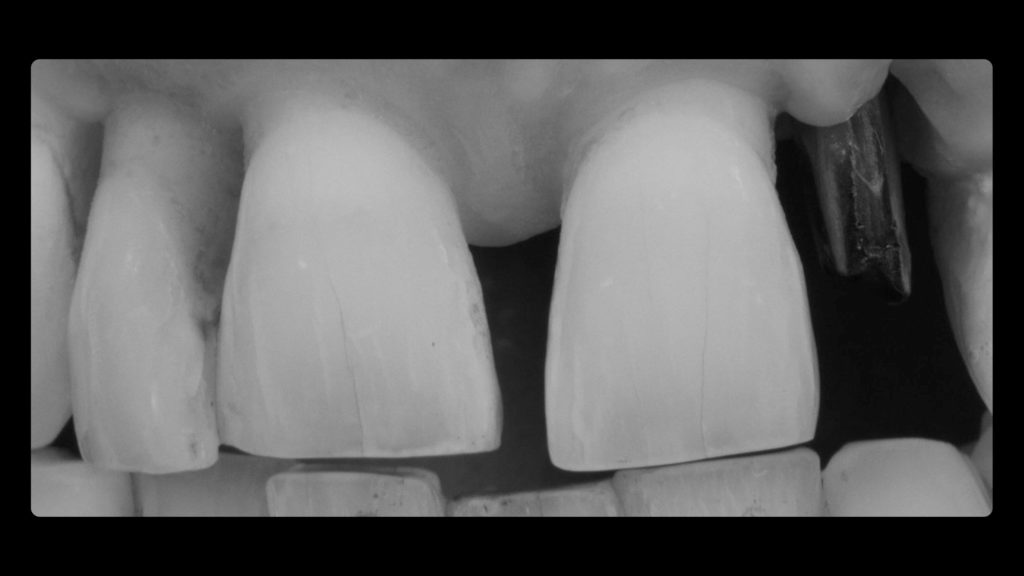

Die Implantatkrone sollte metallkeramisch gelöst werden, was wiederum bedeutete, dass für die entsprechend designte Implantatkrone ein CAD/CAM-gestützt gefertigtes Abutment (vorgefertigt, Schweden & Martina) mit einer Metallkeramik (Ceramco 3, Dentsply Sirona) verblendet werden musste. Es wurde eine zementierte Lösung gewählt, weshalb es keinen Schraubenkanal gab und somit keine Probleme mit dessen Austritt gelöst werden mussten. In den Abbildungen 6a und 6b sind die DSLR-Aufnahmen des Behandlers dargestellt. Die Referenzfarbmuster vermitteln die ungefähre Zahnfarbe, aber nicht alle Informationen und Merkmale, die für die Rekonstruktion des natürlichen Zahns vonnöten sind. Indem man die Belichtung reduziert und den Kontrast sowie die Brillanz in einem Bildbearbeitungsprogramm wie Lightroom (Adobe) erhöht, lässt sich die Histoanatomie des natürlichen Zahns besser darstellen (Abb. 6c).

Auf Wunsch des Patienten sollte der zu rekonstruierende laterale Schneidezahn die Charakteristika des mittleren Inzisiven 21, also seines direkten Nachbarzahns aufweisen. Normalerweise hätte man sich an dem noch verbliebenen lateralen Schneidezahn im ersten Quadranten orientiert, doch leider war auch dessen Zustand nicht ideal, sodass auch dieser in Bälde rekonstruiert werden sollte (Abb. 7a und b). Bei der eingehenden Betrachtung des Zahns 21 stellten wir zwar eine gewisse Ähnlichkeit mit den vom Zahnarzt gewählten Farbmusterzähnen fest, erkannten aber auch relevante Unterschiede. Aus diesem Grund starteten wir die laborseitige Analyse mit polarisierten Aufnahmen (Abb. 8a und b). Da der Patient 49 Jahre alt war, suchten wir gezielt nach charakteristischen Merkmalen natürlicher älterer Zähne und und wurden auch fündig.

Nachdem die Farbanalyse abgeschlossen war, wählten wir die für die keramische Verblendung erforderlichen Massen gemäß der Referenztabelle des Ceramco 3-Systems aus. So wurde gewährleistet, dass wir das, was wir analysiert haben und nachahmen wollten, auch mit den entsprechenden Massen nachahmen konnten (Abb. 10). Den Anfang machte das Opakern des Metallgerüsts. Dafür kam der Ceramco 3-Pastenopaker zum Einsatz, auf den noch zusätzlich der systemimmanente Pulveropaker gestreut wurde. Dies sorgte für eine rauere Oberfläche, an der sich das Licht diffus brechen konnte. Nach dem Brand stellte sich das Ergebnis wie in Abbildung 11 zu sehen dar. Der Behandler hatte als Grundzahnfarbe die A3,5 und für den freiliegenden Wurzelbereich B4 ausgewählt. Dementsprechend wurden die Massen gewählt (Abb. 12 und 13). Darüber hinaus verwendeten wir, wie aus den Fotografien, die mit Kreuzpolfilter angefertigt worden waren, ersichtlich (vgl. Abb. 8a und b), im inzisalen Drittel eine Dentin-Masse mit geringerem Helligkeitswert (Abb. 14 und 15).